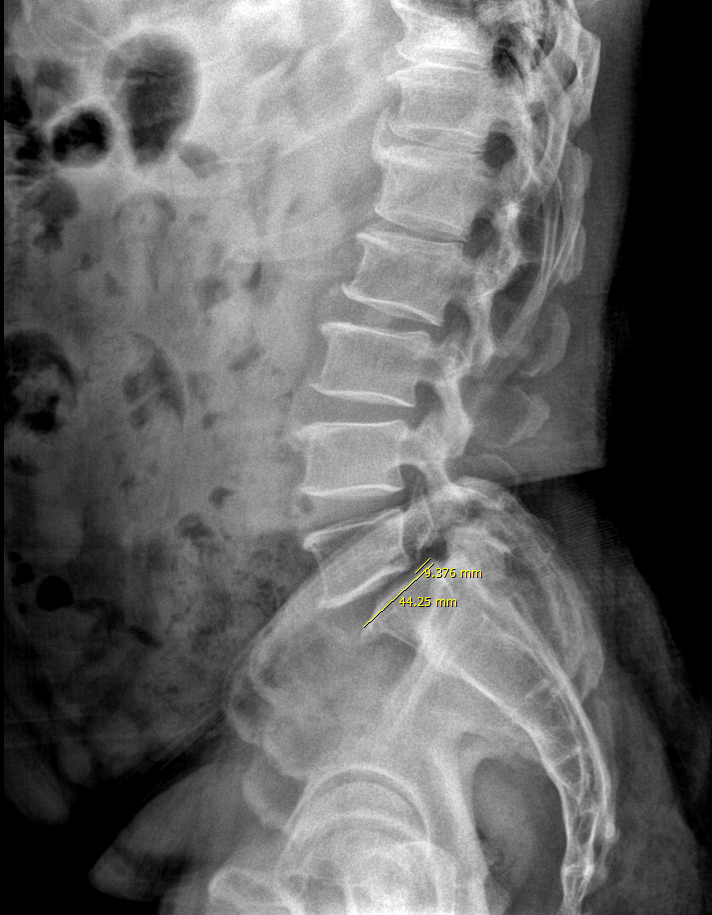

얼마전에 다시 오셨습니다. 꾸준히 받자고 했는데, 거의 1년 8개월만에 오셨습니다.

얼마 전 엑스레이 찍고, 수술 이야기 들으셨다고 합니다.

단순 요통이었는데, 앉아있다가 일어설 때 발바닥을 떼기 어렵고 발바닥이 저리다고 하십니다.

다행히 grade는 변하지 않은 것으로 보입니다. 신경학적 증상이 언제부터 지속되었는지는 환자분이 파악하지 못합니다.

다만 일상생활이 불가할 정도의 통증이 아니고, 전방전위의 상태가 비교적 안정적으로 보존되어있으며, 무엇보다 환자 본인이 수술을 원치 않으므로 증상을 꾸준히 f/u하며 3개월 가량 보존적 치료를 시행해볼까 합니다. 초기에 신경학적 증상이 없었을 때 꾸준히 치료받으셨으면 어땠을까 하는 아쉬움이 있는 분입니다.